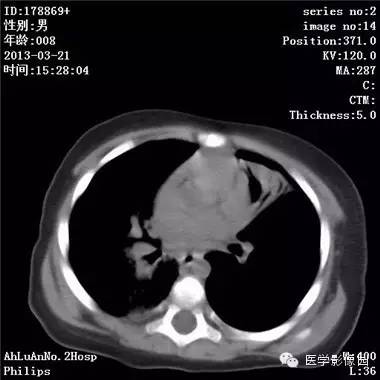

患儿男,8个月,呛咳,发热一周。实验室检查白细胞及中性粒细胞增高。

两肺肺纹理增多、增粗,右肺可见斑片状、片絮状模糊影,边界欠清;左肺上叶见楔形高密度影,内可见支气管征,尖端指向肺门;左肺下叶肺野透亮度增强;另见左肺主支气管内可见块状软组织密度影。

支气管异物(花生米)伴两肺炎症(追问病史,患儿奶奶层于一周前喂食患儿花生米,当时疑似“呛进去”,后来见好了也就没留意)。